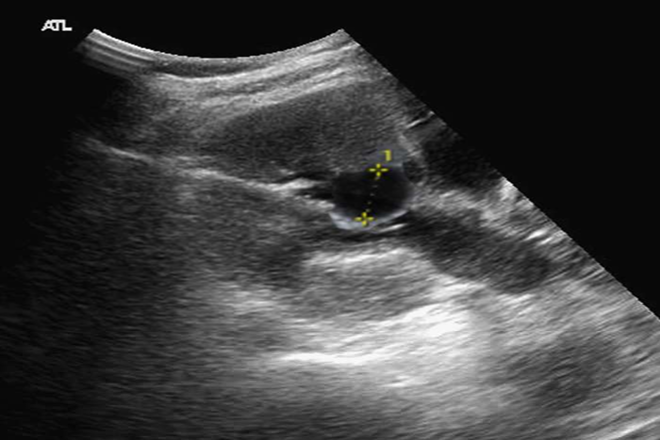

síndrome de ovario poliquístico. Diagnóstico y manejo

El síndrome de ovario poliquístico (SOP), también denominado hiperandrogenismo ovárico funcional o anovulación crónica hiperandrogénica, es una disfunción endocrino-metabólica de alta prevalencia. Su etiología es incierta y se manifiesta por síntomas y signos variados que afectan a cada mujer en forma particular. Entre ellos destacan las irregularidades menstruales, las manifestaciones